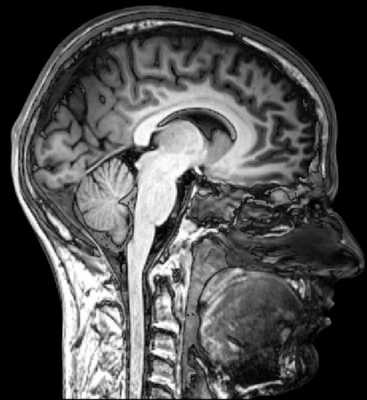

Томографический снимок головного мозга

Головной мозг является самым сложным органом, он насчитывает целых 5 отделов, поэтому так важно знать, что показывает МРТ мозга. Речь идет о самой современной и информативной методике обследования.

МРТ снимки головного мозга четко показывают, есть патологические изменения в его отделах или нет. При их выявлении врач назначает эффективное лечение. Чем раньше начинается терапия, тем больше шансов, что она окажется успешной.

МРТ картина головного мозга позволяет оценить состояние не только мозжечка, но и других отделов, которые отвечают за память и мыслительный процесс. Тщательно обследовать затылочные доли, отвечающие за визуальное восприятие предметов, оценить плотность серого и белого вещества.

МРТ головы визуализирует различные мозговые отделы, дает их характеристику. Главной целью такой диагностики является обнаружение пораженных участков в мозге, определения их формы, размеров, характера и точной локализации.